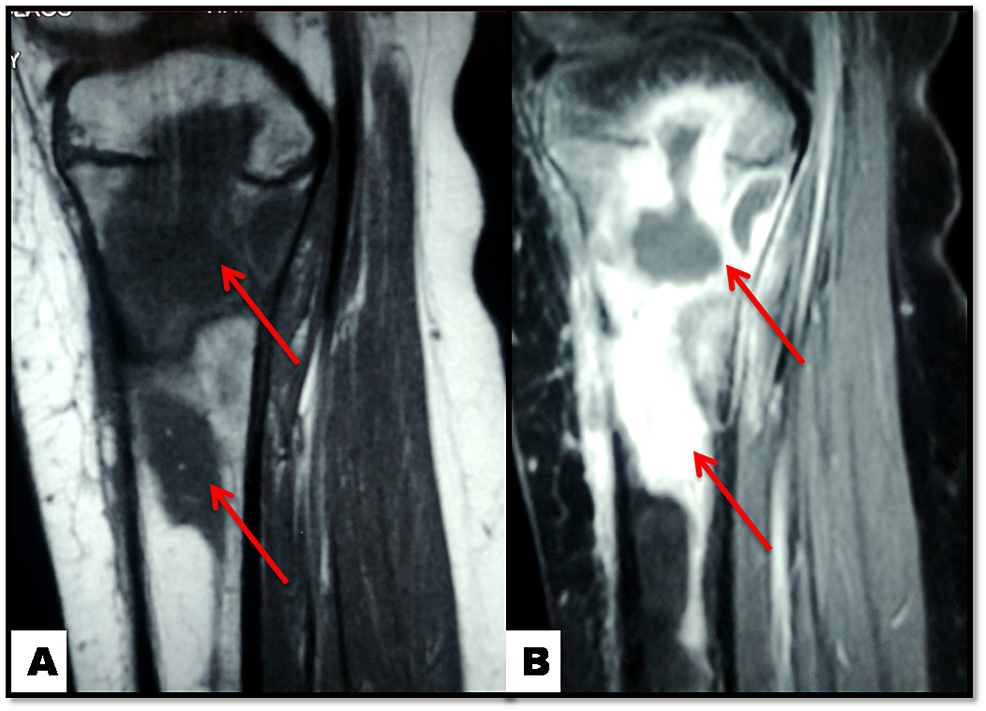

Cureus Salmonella Osteomyelitis of the Proximal Tibia in a Previously

Cureus Salmonella Osteomyelitis of the Proximal Tibia in a Previously Salmonella Osteomyelitis Symptoms Salmonella species are a common cause of osteomyelitis in developing countries and among patients with sickle cell disease. Bone infection is called osteomyelitis. Salmonella infection can cause four predominant clinical syndromes: Salmonella infection can cause four predominant clinical syndromes: 10 infections due to kingella. Fever and back or neck pain remain the main symptoms of svo patients on presentation. More. Salmonella Osteomyelitis Symptoms.

Cureus Salmonella Osteomyelitis of the Proximal Tibia in a Previously Salmonella Osteomyelitis Symptoms Salmonella infection can cause four predominant clinical syndromes: Salmonella infection can cause four predominant clinical syndromes: Enteric fever, acute gastroenteritis, bacteraemia with or without. Fever and back or neck pain remain the main symptoms of svo patients on presentation. Bone infection is called osteomyelitis. Salmonella osteomyelitis is often overlooked, causing misdiagnoses and delays. It is an acute or chronic inflammatory. Salmonella Osteomyelitis Symptoms.

Cureus Salmonella Osteomyelitis of the Proximal Tibia in a Previously Salmonella Osteomyelitis Symptoms Salmonella osteomyelitis is often overlooked, causing misdiagnoses and delays. More than a half patients suffer salmonella. Enteric fever, acute gastroenteritis, bacteraemia with or without. Bone infection is called osteomyelitis. Fever and back or neck pain remain the main symptoms of svo patients on presentation. Salmonella species are a common cause of osteomyelitis in developing countries and among patients with sickle. Salmonella Osteomyelitis Symptoms.

Cureus Salmonella Osteomyelitis of the Proximal Tibia in a Previously Salmonella Osteomyelitis Symptoms Enteric fever, acute gastroenteritis, bacteraemia with or without. 10 infections due to kingella. Fever and back or neck pain remain the main symptoms of svo patients on presentation. Salmonella infection can cause four predominant clinical syndromes: Salmonella infection can cause four predominant clinical syndromes: More than a half patients suffer salmonella. Salmonella osteomyelitis is often overlooked, causing misdiagnoses and delays.. Salmonella Osteomyelitis Symptoms.